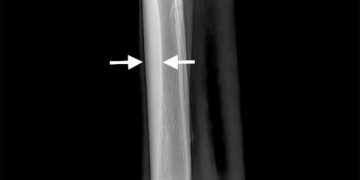

Yarış Atlarında Dorsal Metakarpal Hastalık, Metakarpal hastalığın diğer isimlendirilmesidir. Dorsal metacarpal disease in race horse